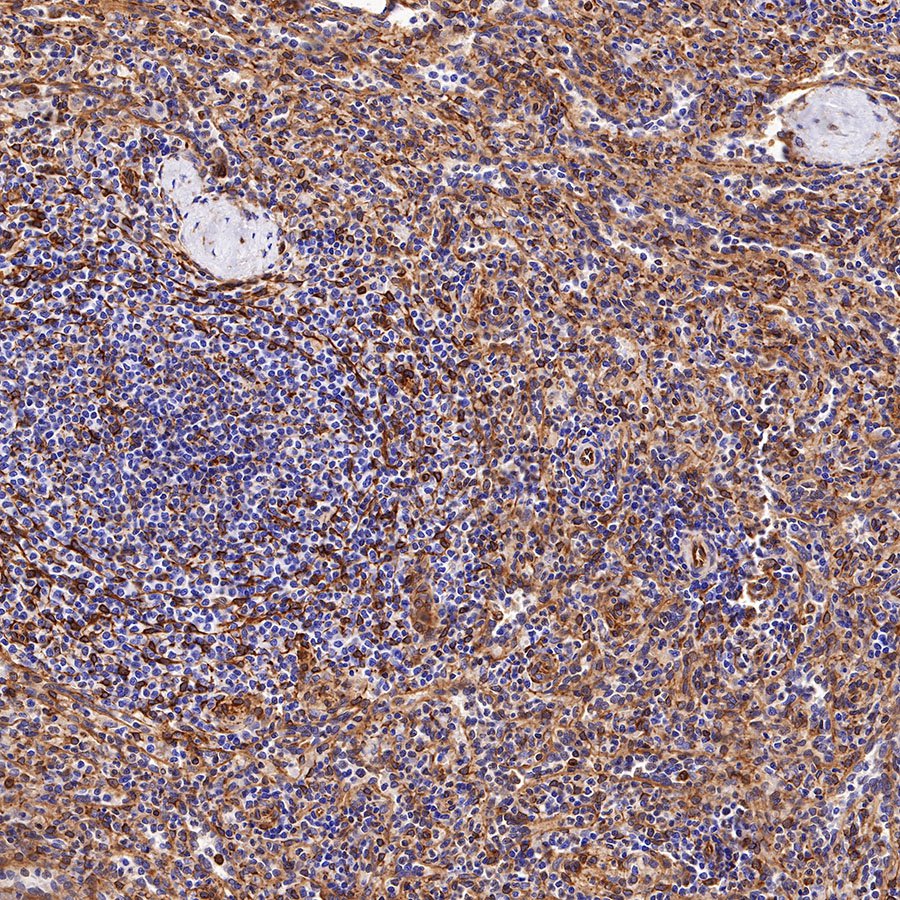

Picture

Picture

Immunohistochemistry